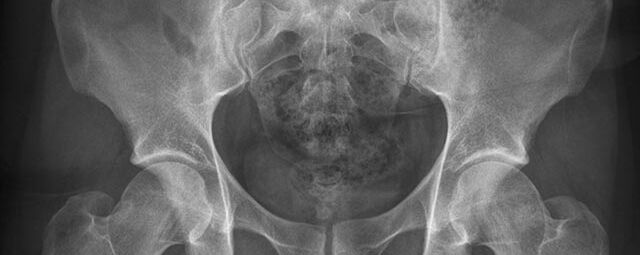

Röntgen Knochen

Röntgenaufnahme einer Hand

• Fraktur

• Arthrose

• Rheumatische Gelenkerkrankungen

• Degenerative Veränderungen der Wirbelsäule

• Knochentumor

• Osteoporose

• Therapiekontrolle nach OP am Skelettsystem

• Vollautomatische Erstellung von Ganzbein- und Ganzwirbelsäulenaufnahmen